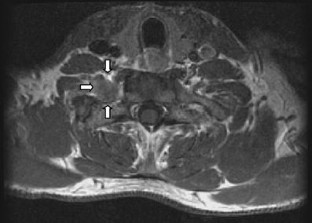

T-cell lymphoblastic lymphoma is a rare form of non-Hodgkin lymphoma, which shows preponderance for young men. Most common symptoms are painless swelling of lymph nodes, accompanied by B symptoms and large mediastinal masses. Most often, an involvement of the nervous system is due to paraneoplastic symptoms or side effects of treatment. In a literature research, we could not find a case with affection of a cervical nerve root as the first symptom for T-cell lymphoblastic lymphoma. A 39-year-old man presented with right-sided C8 radiculopathy, including pareses and paresthesia. Since the magnetic resonance image disclosed a right-sided mass lesion in the region of the neuroforamen C8, compressing the corresponding nerve root, a schwannoma was suspected. The tumor was removed using a dorsal approach. Neuropathological examination revealed the diagnosis of T-cell lymphoblastic lymphoma. The patient underwent diagnostic staging and received further treatment. He experienced a very grim course and succumbed to his disease 12 months after surgery. T-cell lymphoblastic lymphoma is a rare disease, and tropism of lymphoma cells to neural structures is seldom encountered. However, the presence of radiculopathy, together with signs, referring to B symptoms, should prompt the physician to consider this coincidence in the differential diagnosis of schwannoma.

This paper is interesting for neurosurgeons dealing with spinal tumors and demonstrates that lymphomas could be located everywhere within the central nervous system. High-grade lymphomas should be taken into consideration in the preoperative discussion, especially when MR imaging of the lesion shows such an inhomogeneous contrast enhancement and the clinical signs and symptoms in young patients are as rapidly deteriorating as demonstrated.